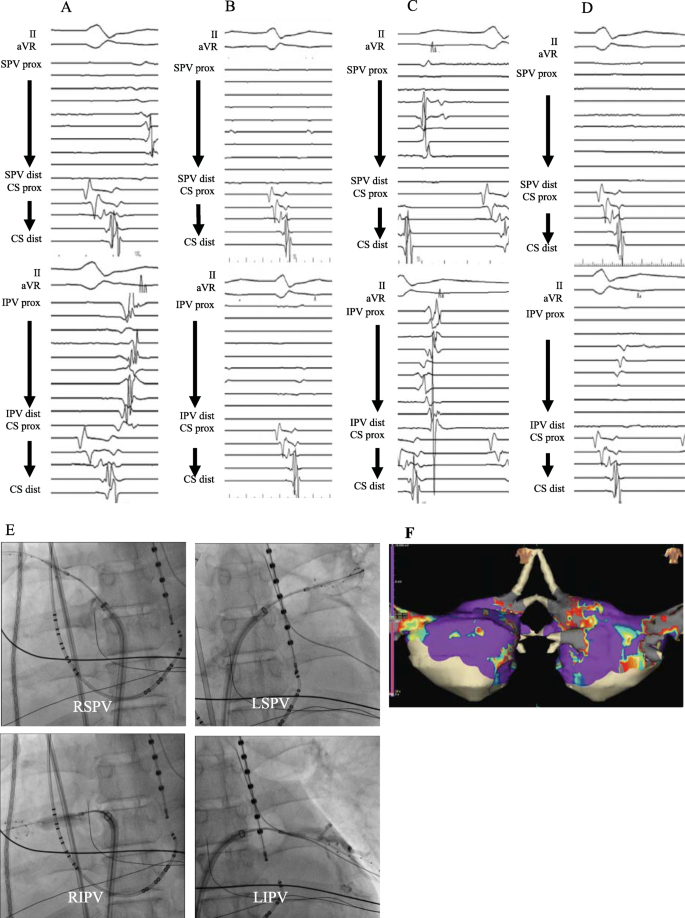

Pulmonary vein isolation using cryoballoon. a: Baseline intracardiac electrograms of the left pulmonary veins before isolation. b: Intracardiac electrograms after the left pulmonary vein isolation. c: Baseline intracardiac electrograms of the right pulmonary veins before isolation. d: Intracardiac electrograms after the right pulmonary vein isolation. e: Fluoroscopic AP image demonstrating positions of the cryoballoon for all pulmonary veins. f: Three-dimensional map with grey area representing ablated area by pulmonary vein isolation using cryoballoon. CS, coronary sinus; dist, distal bipole; prox, proximal bipole; IPV, inferior pulmonary vein; LIPV, left inferior pulmonary vein; LSPV, left superior pulmonary vein; RIPV, right inferior pulmonary vein; RSPV, right superior pulmonary vein; SPV, superior pulmonary vein

On the same day, prior to the procedure, trans-oesophageal echocardiography was performed and found no detectable thrombus in the left atrium (LA). PVI to the AF and cavotricuspid isthmus ablation to common-type AFL were planned. Fortunately, the patient’s haemodynamics did not collapse at the time of ablation, we performed our institutional standard procedure including 3-D mapping. The cryoballoon was chosen as a PVI catheter because cryoballoon ablation was expected to have a shorter procedure time and lesser thrombogenic effect than other catheter types [7, 12]. A 20-polar catheter (Response™; Abbott, St. Paul, MN, USA) was placed in the coronary sinus. A three-dimensional electroanatomical mapping was constituted by a cardiac mapping system (EnSite velocity™; Abbott). Transseptal access was obtained using the standard Brockenbrough needle technique with intracardiac ultrasound and fluoroscopic guidance, and an 8-Fr SL0 sheath (Swartz™; Abbott) was inserted into the LA. The cardiac geometry including all pulmonary veins (PV) was established using a 20-pole circular mapping catheter (Reflexion Spiral™; Abbott). No left atriography was conducted because of acute kidney injury. Then, we changed the SL0 sheath to a steerable sheath (FlexCath Advance™; Medtronic Inc., Minneapolis, MN, USA) and inserted a 28-mm second-generation cryoballoon catheter (Arctic Front Advance™; Medtronic Inc.). In each PV, the cryoballoon was placed at the ostium of each PV in turns, and cryoballoon ablation was performed after complete occlusion of each PV as confirmed by the minimum amount of contrast agent. During cryoenergy deliveries, the oesophageal temperature and diaphragmatic compound motor action potential were monitored to avoid LA-oesophageal fistula and phrenic nerve injury. Additional touch-up radiofrequency ablation using FlexAbility™ (Abbott) to the residual LA-PV conduction gap at the bottom of the right inferior PV after cryoballoon ablation was conducted, and complete PVI was achieved (detailed PVI procedural data is shown in Table 1 and Fig. 1). Subsequently, a 20-polar catheter (Livewire™; Abbott) was placed around the tricuspid annulus, confirming that the AFL was cavotricuspid-isthmus dependent. The cavotricuspid isthmus ablation for common-type AFL was performed by standard procedure using radiofrequency ablation catheter and successfully achieved bidirectional block. The whole procedure was finished uneventfully and restored sinus rhythm and blood pressure of approximately 110 mmHg.